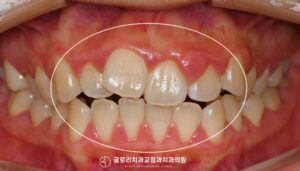

안녕하세요 망우동 치과 김정은 원장입니다. 치아 사이가 벌어져있고 앞니가 앞으로 나와있는 경우 보기에도 신경 쓰이지만 교정이 필요한 구조적인 문제가 동반되는 경우가 많습니다. 특히 위턱이 하악보다 상대적으로 앞에 위치하는골격성 2급 부정교합이…